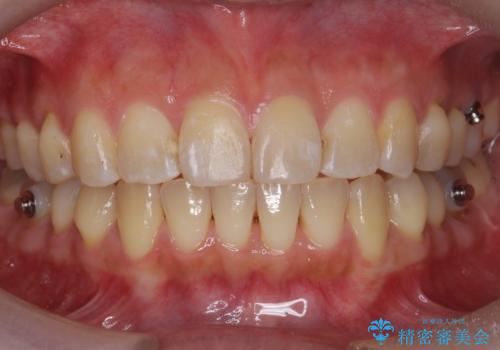

前歯を引っ込めたい 歯を抜かずにマウスピースで

- 前歯の突出を主訴に来院。

上の奥歯を後ろに下げて治療をしました。

矯正用のミニスクリューを使用しています。

上の前歯もIPR(エナメル質をわずかに削る処置)を行っています。